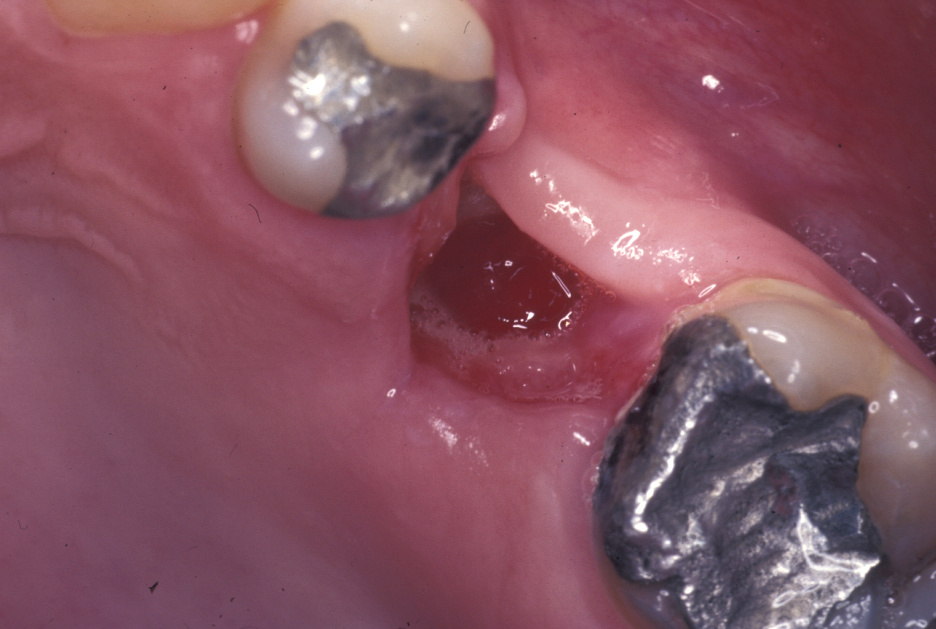

An oroantral fistula (a communication between the oral cavity and the maxillary sinus (antrum) is a common condition. Lining of the antrum may prolapse through such a fistula (Figure 1), or the fistula will have become lined with epithelium (thin, surface-covering tissue) as shown in Figure 2.

Figure 2: Typical oroantral fistula, the communication has become lined with epithelium.